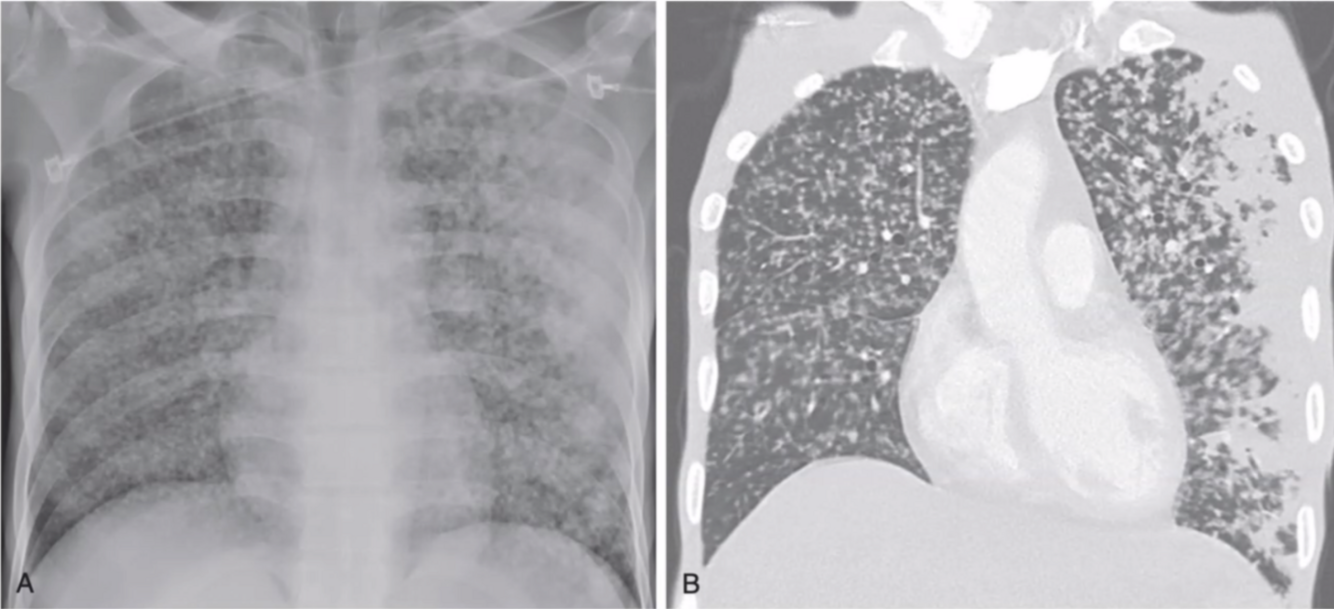

Describe el patrón y a qué presentación de tuberculosis pertenece?

A

• Patrón micro-nodular, diseminado, bilateral

• Miliar